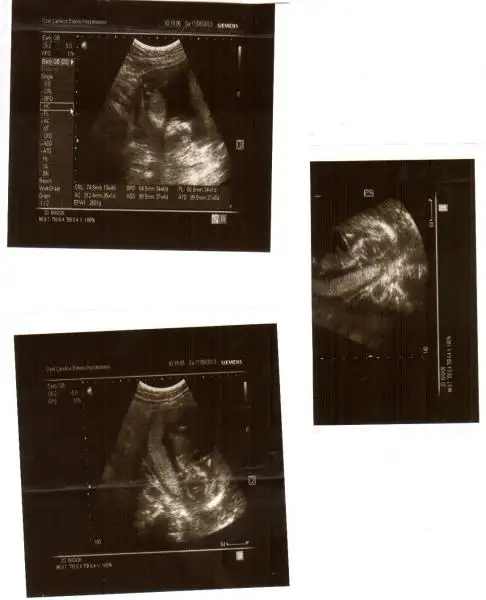

kızlar benim resimlerede bi yorum yapın ne acaba?ben anlayamadım.çabuk yazın çok merak ediyorum![]()

hayret bu resme gore kiz dr erkek demis gerci resim tamda net degil allhim tamamina erdirsin